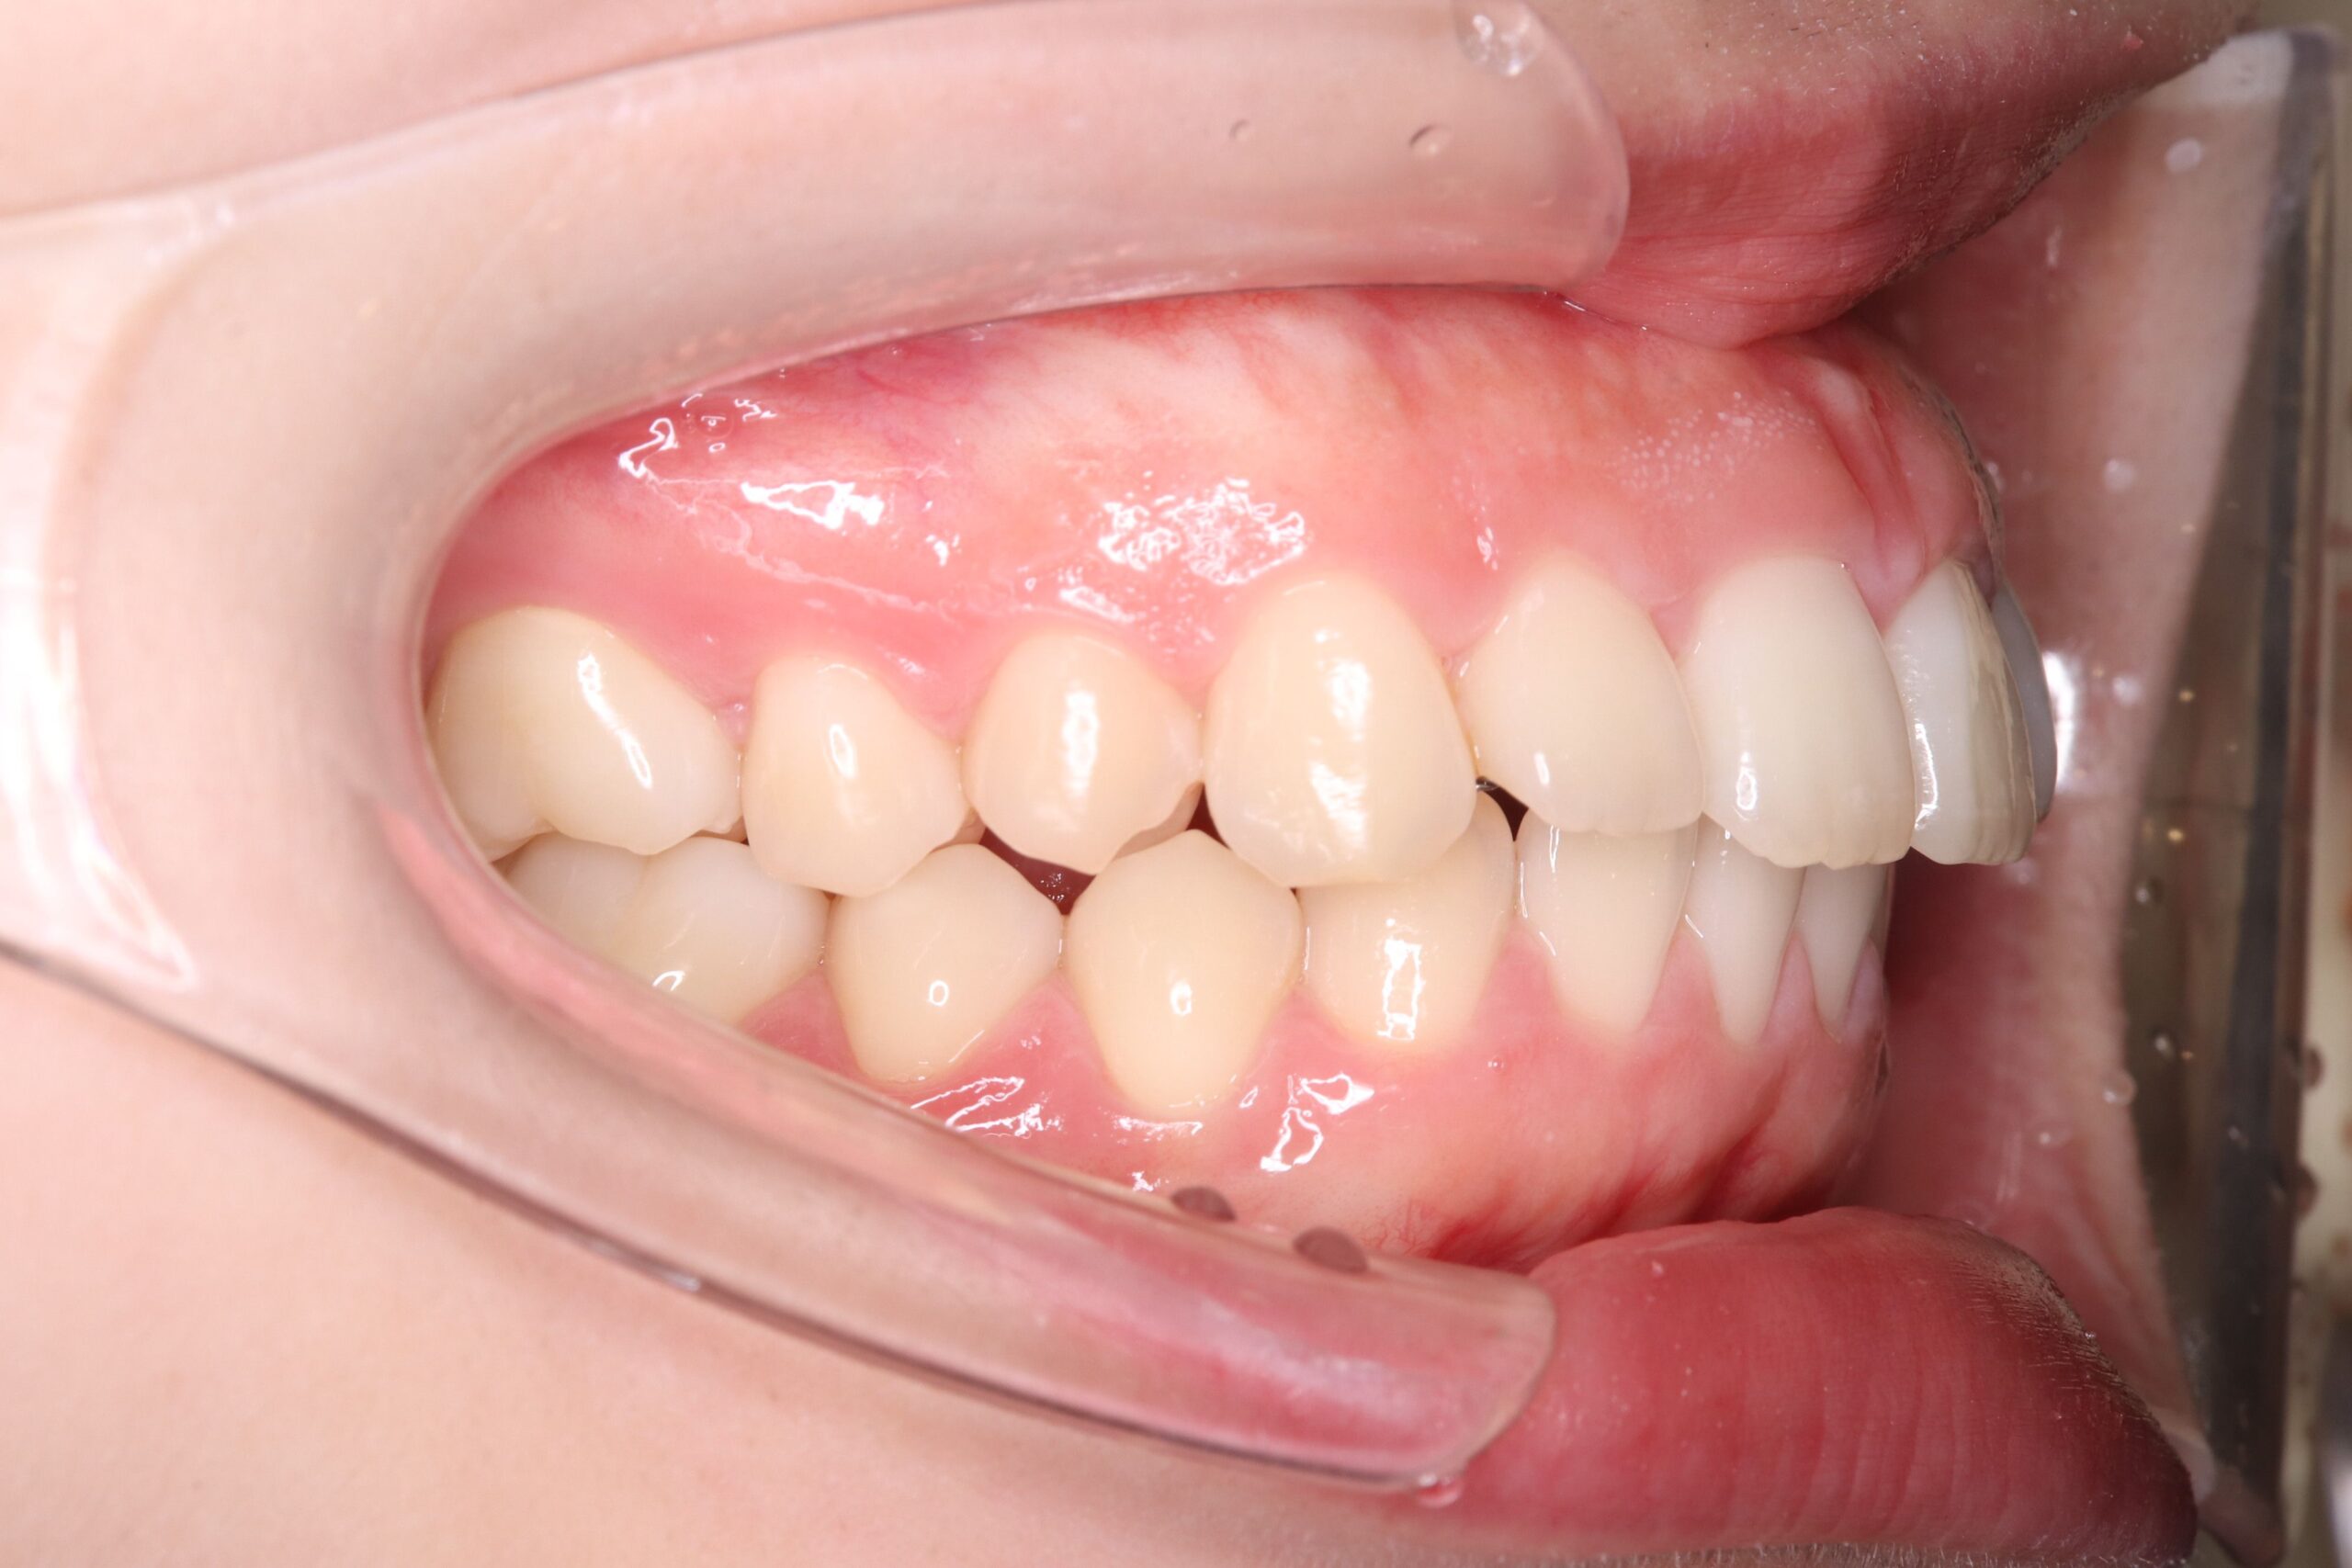

症例:非抜歯+アンカーで改善したケース

症例:ガタガタ+軽度の口元突出 → 非抜歯+アンカーで改善

非抜歯アンカー矯正の初診時|奈良の矯正歯科

初診時

非抜歯アンカー矯正の治療完了|奈良の矯正歯科

治療完了

インプラントアンカーで上の歯列全体を後方に移動。抜歯せずにガタガタと口元の突出感を改善しました。